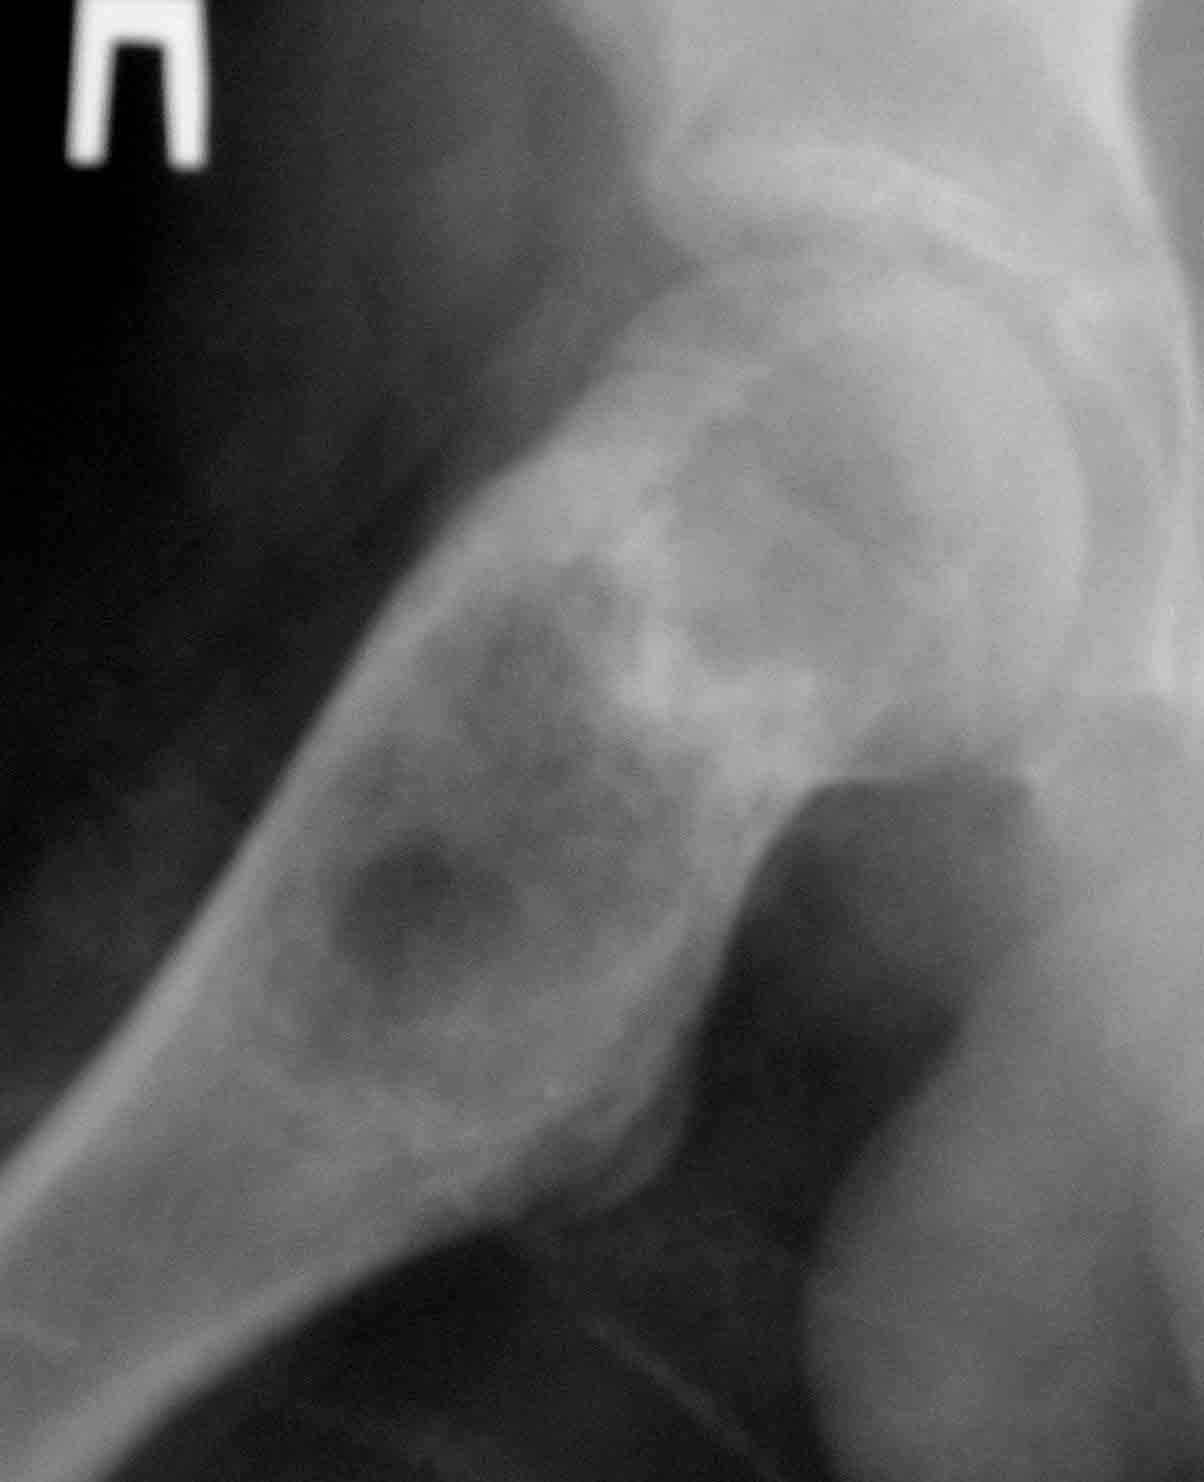

Дабы не уводить в офтопик вопрос о несросшемся переломе бедра, хочу добрым словом упомянутьколлапан - доступный и эффективный российский продукт, который судя по публикациям на форуме не нашел еще должного распространения в повседневной практике. Чтобы не быть обвиненным в рекламе или личной заинтересованности скажу, что работаю я в Казахстане, где большинство последних российских разработок не прошло регистрацию( отдельный вопрос почему?) и коллапан завозят родственники пациентов из соседних сибирских городов. За тридцать лет практики многократно возникали ситуации в которых остро чувствовалась проблема материала для заполнения костных дефектов- от открытых переломов до дефектов при секвестрэктомиии и удаления кистозных опухолей. Риск аутопластики в инфицированную среду или дефицит донорской кости у детей, повсеместное закрытие лабораторий консервации тканей, высокая стоимость зарубежных остеоиндуктивных материалов делают коллапан одним самых доступных материалов в exUSSR \простите за пафос\. В нашем отделении мы применяем коллапан в гранулах с антибиотиком для пристеночной пластики при удалении секвестров при послеоперационных и посттравматических остеитах, при остеосинтезе ложных суставов и заполнении костных дефектов. Коллапан не может применяться в ситуациях где имплантату необходима опорная функция, но это уже другая песня. Привожу пример 15 летнего пациента с обширной фиброзной дисплазией проксимального бедра, которого я оперирован в ноябре 2005, контрольный снимок от 3-2006.

Произведена подвертельная трепанация, кюретаж и рыхлое заполнение гранулами коллапанаГ полости, ушло до 100 куб см гранул. Иммобилизация не проводилась, нагрузка на ногу разрешения через 5 мес, сейчас подросток активно отдыхает на каникулах. Аваскулярный некроз головки вроде не предвидится, думается, что в процессе роста кисты коллатеральное кровообращение сформироваласьдостаточно, о судьбе ростковой зоны можно будет говорить через год. Кстати в одном НИИ ему былапредложена операция эндопротезирования. Первые 2 мес

Под рукой нашелся повод для похожих эмоций. Патологический перелом на месте рецидива костной кисты у девочки 16 лет (обсуждали этот случай

года два назад). Ни коллапана, ни трансплантатов, ничего другого в очаг не вводили, кроме нержавеющей стали. Она, видимо, тоже остеоиндуктор - видно, что на месте пустоты через несколько месяцев кость.